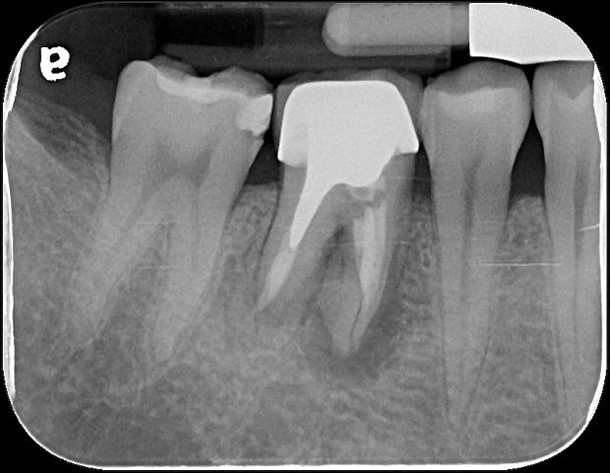

治療前,牙齒長膿胞

治療前,牙骨已破壞